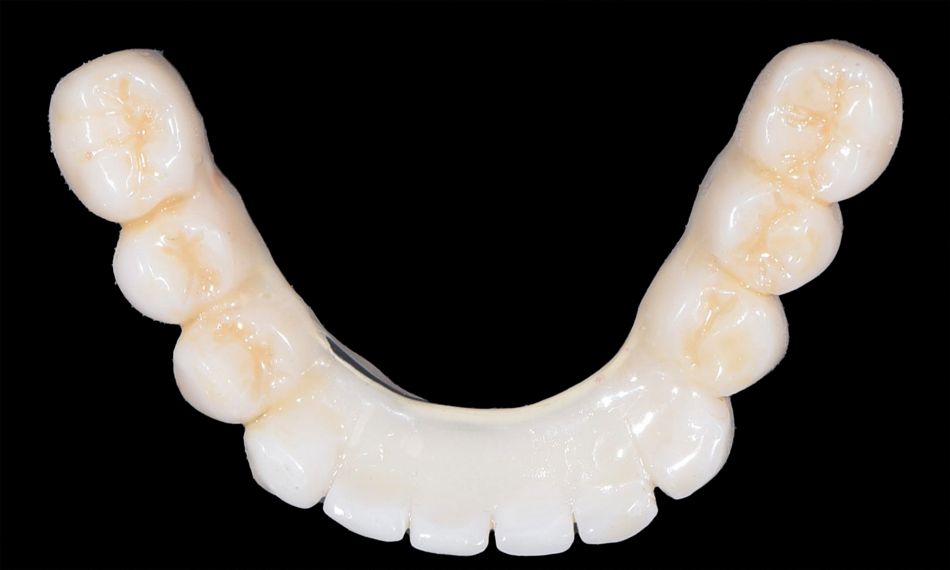

The lab stage involved meticulous attention to detail in manufacturing the full arches. The prosthetic restoration of choice was a maxillary and mandibular metal reinforced acrylic prosthesis. The lab provided the finalized prosthesis including the LOCATOR FIXED® Housings with pre-assembled black processing inserts to the dental practice.

The next step involved placing the LOCATOR FIXED® Inserts into the housings. The selection of LOCATOR FIXED® Inserts was tailored to the specific indication. In cases involving five or more implants per arch, tan and blue shaded inserts are utilized. This procedure achieved by aligning the insert with the housing and applying firm downward pressure with the LOCATOR® Systems Core Tool until the insert snapped securely into place (Figs. 23-28).